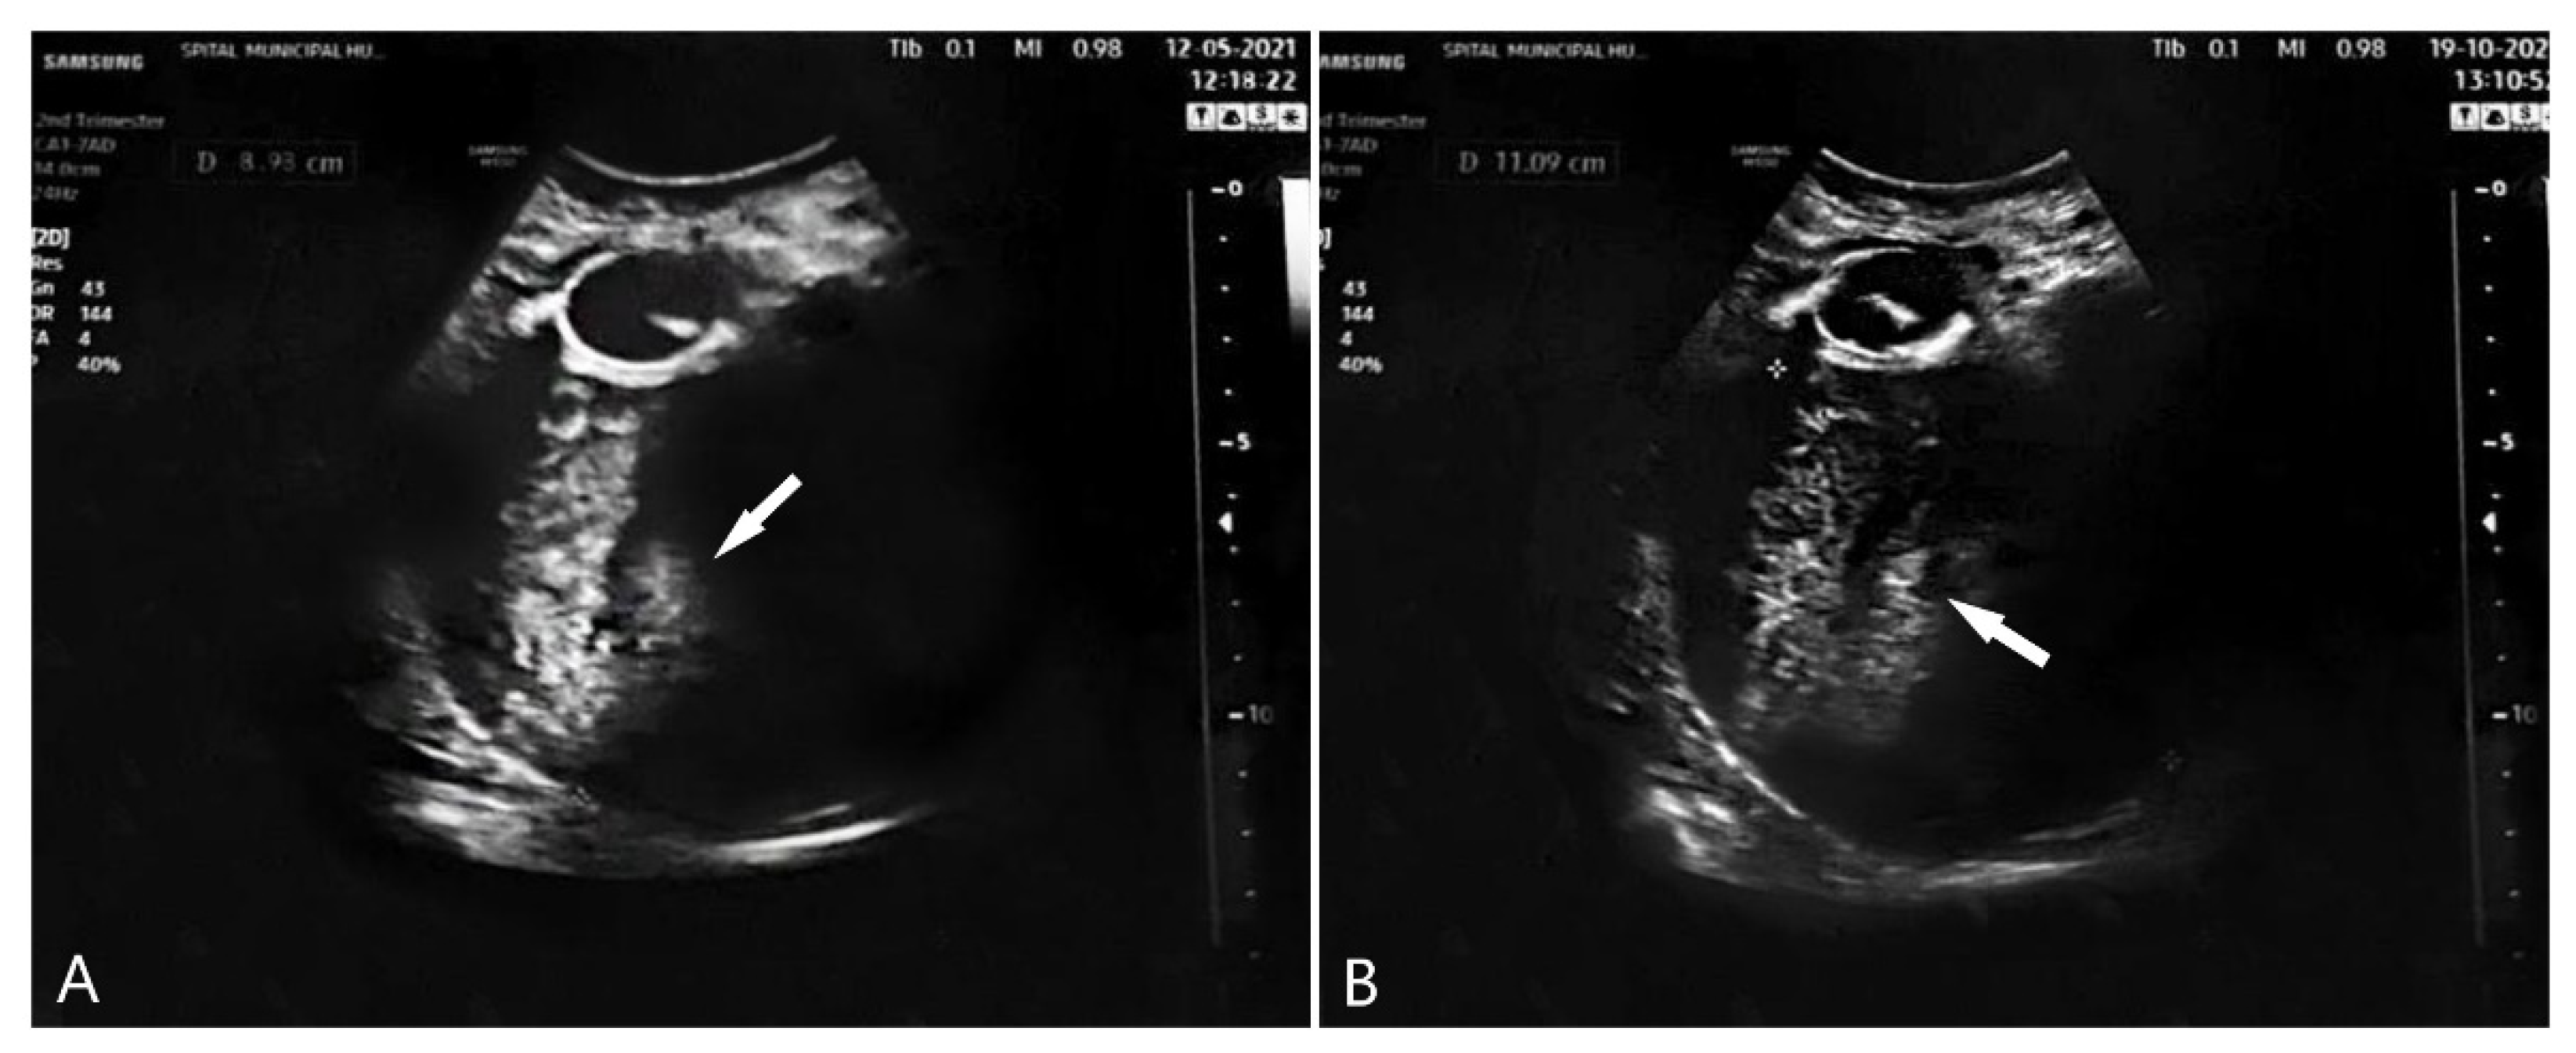

2. Case Presentation